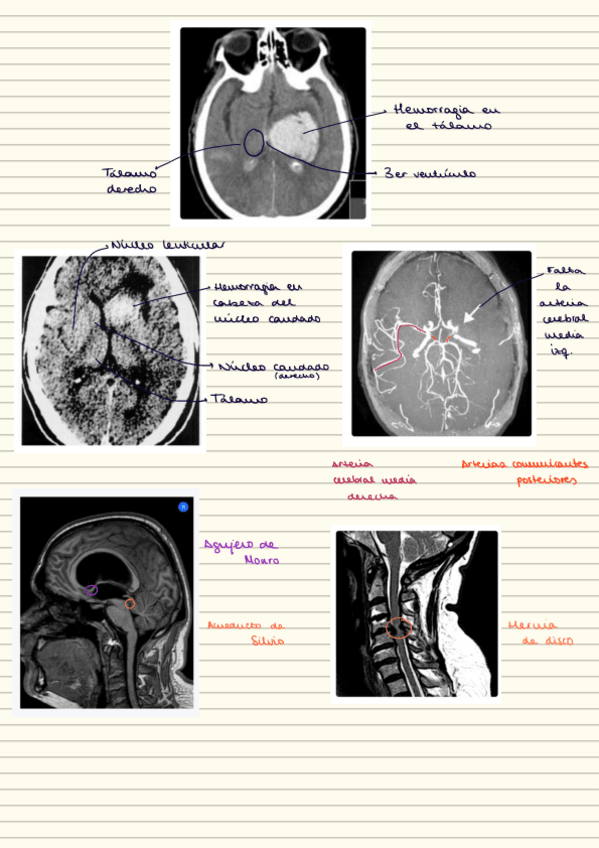

He publicado nuevos apuntes de 2º Anatomía Humana II: practicas-neuroanatomia.pdf

He publicado nuevos apuntes de 2º Anatomía Humana II: practicas-imagenes-resonancias.pdf

He publicado nuevos apuntes de 2º Anatomía Humana II: Casos-clinicos-practicas.pdf